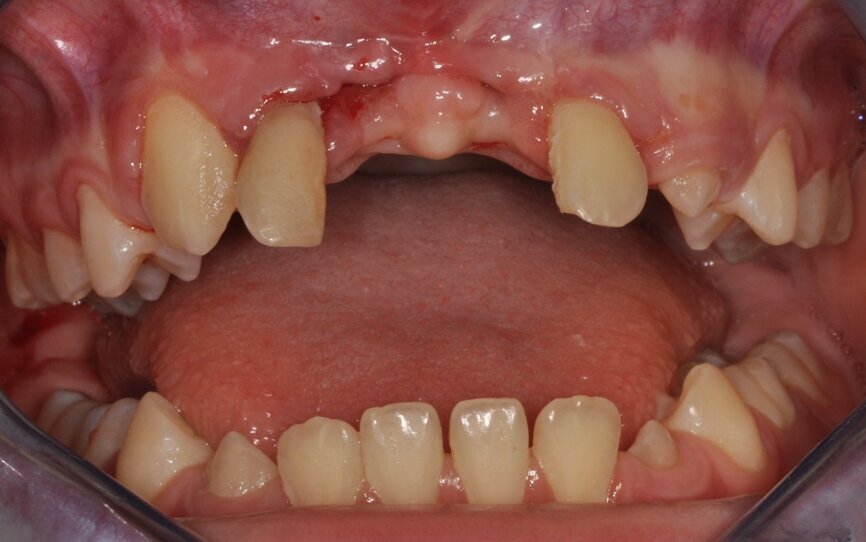

Miesiąc po ekstrakcji zębów przeprowadzono zabieg autotransplantacji (Ryc. 8). W znieczuleniu dożylnym krótkotrwałym i miejscowym nasiękowym 4 amp. 4% Ubistesin Forte nacięto płat pełnej grubości trapezowy od 12 do 22. Stwierdzono rozległy ubytek kostny o charakterze krateru, bez blaszki przedsionkowej. Wiertłem chirurgicznym i implantologicznym wykonano miejsce biorcze na donory (Ryc. 9). Kolejno usunięto zęby mleczne 75 i 85 oraz pobrano zawiązki zębów stałych 35 i 45 w fazie rozwoju korzenia R3/4 wg Moorresa. Wprowadzono na miejsce biorcze oraz całkowicie pokryto płatem, zszywając nierozpuszczalnym syntetycznym monofilamentem poliamidowym o rozmiarze 5,0 (Seralon®). Miejsce dawcze zaopatrzono gąbką kolagenową w kształcie stożka (Parasorb® Cone), (Ryc. 10). Po zabiegu zalecono Augmentin 1000 mg (2 x 1 tabl.), Ibuprofenum 200 mg (3 x 1 tabl.), Enterol (2 x 1 tabl.), Reparil (3 x 2 tabl.). Po 14 dniach usunięto szwy. Gojenie przebiegało bez powikłań. Kontrole radiologiczne i kliniczne przeprowadzono 1, 3, 6 (Ryc. 11), 12 i 18 miesięcy po zabiegu. Na czas leczenia pacjenta zaopatrzono płytka ortodontyczną uzupełniającą braki zębów 11 i 21.

Ryc. 8_Stan miejscowy bezpośrednio przed autotransplantacją.